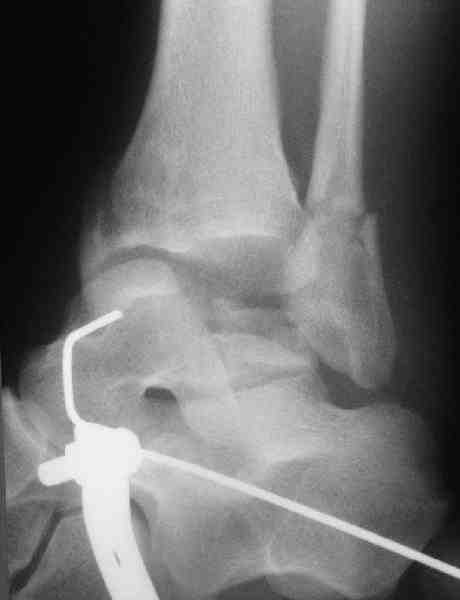

Решили не связываться с остеосинтезом, а сделать сразу берцово-пяточный блок. Снимки в приложении.

По завершении удлинения, наверно, заштифтуем.

Комментарии/критика приветствуются.